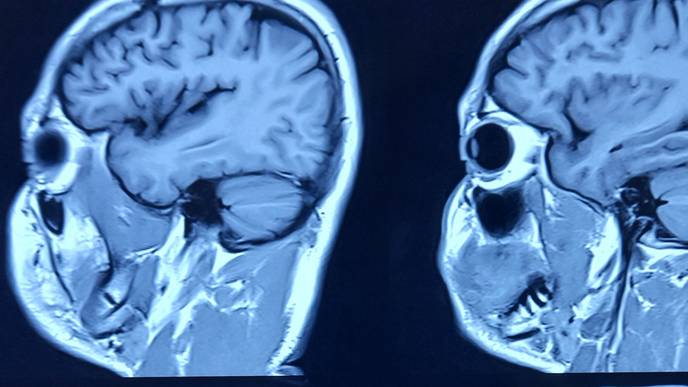

The human brain, a marvel of complexity, operates as an intricate network where various regions collaborate structurally and functionally. These interactions forge complex patterns that underpin the diverse functionalities of the brain. Understanding these complex functions necessitates a deep dive into the brain's networks and the sophisticated interconnections and communication modalities they encompass. Moreover, the exploration of brain network mechanisms opens new vistas in the study of diseases marked by abnormalities in brain function, such as brain injuries and mental disorders, making the investigation of the brain's complex network system paramount for a holistic grasp of its functionalities.

Graph Theory, the bedrock of network science, has found extensive application in dissecting the attributes of complex networks, including those of the brain. It lays out a framework for examining the topological structures of these networks, unveiling pivotal organizational details of functional brain networks across both micro and macro scales. Despite graph theory's immense analytical potential, the intricacy of existing professional imaging data processing software—often demanding high-level programming acumen—has been a bottleneck, hampering the broader adoption and application of these analytical methods.

Addressing this challenge, Dr. Chao-Gan Yan and his team from the Magnetic Resonance Imaging Research Center at the Institute of Psychology, Chinese Academy of Sciences, have innovated beyond their previously acclaimed brain imaging processing platform (DPARSF/DPABI/DPABISurf, cited in over 5,000 research works, with the DPABI software paper being distinguished as one of the top 0.01% highly cited papers by ESI and featured among the hot papers in the Chinese medical field for 2015-2019). They unveiled DPABINet, a pioneering platform that amalgamates cutting-edge image processing modules like Brain Connectivity Toolbox, FSLNets, BrainNet Viewer, Circos, SPM, PALM, among others, leveraging docker technology to furnish a user-friendly, cross-platform interface and algorithms. DPABINet's intuitive graphical interface (GUI) empowers users to seamlessly construct brain networks, conduct graph theory analysis, and perform statistical analysis and result visualization with a single click, eliminating the need for programming or scripting expertise. Additionally, DPABINet enhances the research on brain structural networks derived from diffusion-weighted imaging, providing a robust analysis framework for brain structural fiber networks predicated on DPABIFiber's preprocessing results.